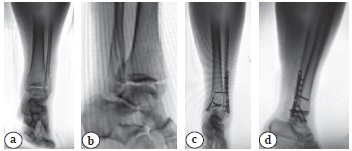

Следует отметить, что в зоне риска при таком доступе находится икроножный нерв, который располагается в подкожной жировой клетчатке как раз в зоне разреза. Для профилактики повреждений этого нерва идентифицировали его в операционной ране и выполняли его отведение в сторону с последующей защитой от травматизации пластинчатыми крючками. Собственную фасцию голени рассекали вдоль линии кожного разреза, сухожилия малоберцовых мышц также отводили медиально или латерально в зависимости от формируемого подхода к заднелатеральной поверхности латеральной лодыжки или к заднему краю ББК. Для обнажения и необходимой визуализации последнего также рассекали глубокую фасцию и отводили медиально сухожилие длинного сгибателя большого пальца стопы, защищавшее задний большеберцовый сосудисто-нервный пучок. При сочетанном повреждении латеральной лодыжки и заднего края ББК первоначально выполняли репозицию и фиксацию фрагмента Фолькмана, что позволяло частично восстановить дистальный межберцовый синдесмоз и облегчало последующий остеосинтез латеральной лодыжки. При этом ориентировались на сопоставление «зубец в зубец» верхушки отделенного фрагмента Фолькмана и соответствующего места на дистальном метаэпифизе ББК. Для создания межфрагментарной компрессии применяли временное наложение остроконечных костодержателей, введение спонгиозных винтов 4,0 мм с короткой резьбой, ориентируя последние перпендикулярно плоскости перелома и параллельно плоскости суставной поверхности, стараясь расположить их в субхондральном слое ББК. При этом у 9 (31,0%) пациентов с достаточно большим фрагментом заднего края ББК, не имеющим тенденции к проксимальному смещению, его фиксацию проводили только винтами (рис. 1).

Рис. 1. Перелом лодыжек типа 44-В3 и исход операции остеосинтеза у пациентки 46 лет:a, b — первичные рентгенограммы в прямой и боковой проекциях;с, d — послеоперационные рентгенограммы — фрагмент заднего края ББК фиксирован двумя 4,0 мм спонгиозными винтами